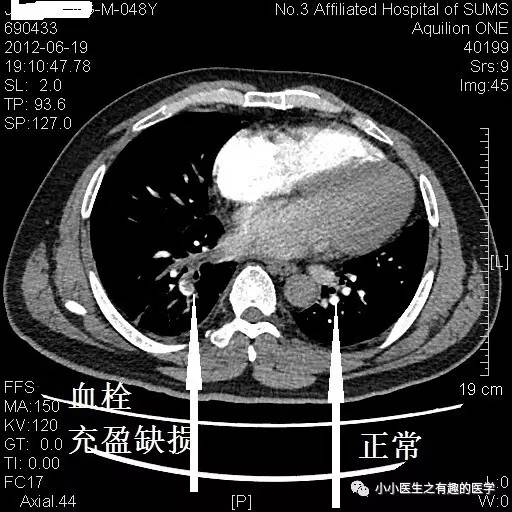

再来一例。我读研究生期间的病人。

小小的充盈缺损。

看小小血栓,也不难。